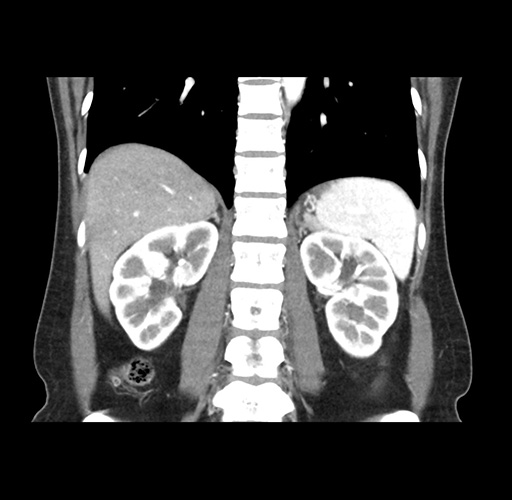

Imaging Analysis

Look through the patient's CT scan to identify any areas of concern for the necessary procedure.

Based on your CT findings, which issue(s) would give reason for "planned slowing down moment(s)" in this case?

Considering a standard left lateral sectionectomy procedure, what step(s) of the operation would you do differently in this case ?